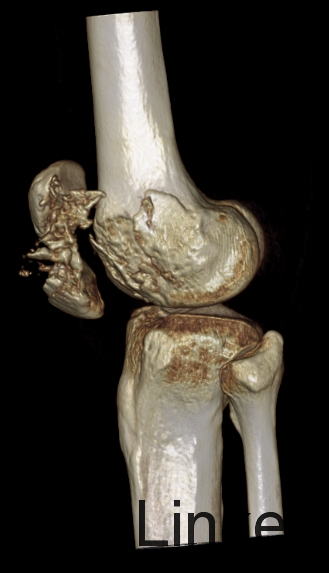

患者自述于2014年4月24日11点左右自马车坠落,摔伤致左膝关节疼痛、流血、活动受限,患者于当地医院行左膝X线检查,提示:左髌骨骨折,包扎,为进一步处理。患者现无意识障碍,无视物不清,无头晕、头痛,无恶心、呕吐,无胸闷及呼吸困难,无腹胀、腹痛。现平素饮食睡眠良好,二便如常。发病近期体重无明显下降。

左膝见一长约10cm的开放口,压痛(+)。未触及骨擦感及异常活动,未闻及骨擦音,患肢无明显 麻木,左下肢血运良好,余肢体查体未见明显异常。